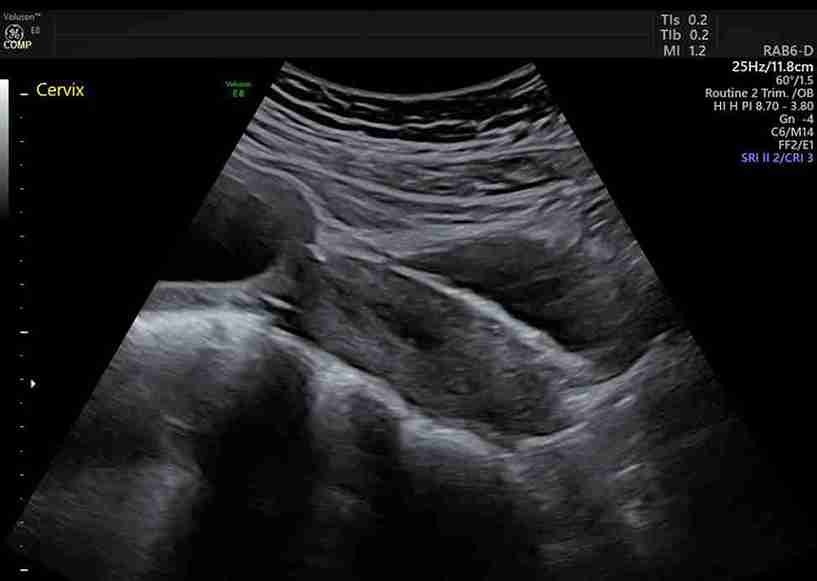

- Daha önce LEEP veya konizasyon gibi bir CIN tedavisi görmüş olmak, nadiren de olsa erken doğum veya servikal yetmezlik riskini bir miktar artırabilir. Bu nedenle, böyle bir geçmişiniz varsa gebelik takibinizi yapan doktorunuzu mutlaka bilgilendirmelisiniz. Doktorunuz gebelik sırasında rahim ağzı uzunluğunuzu ultrason ile takip edebilir.